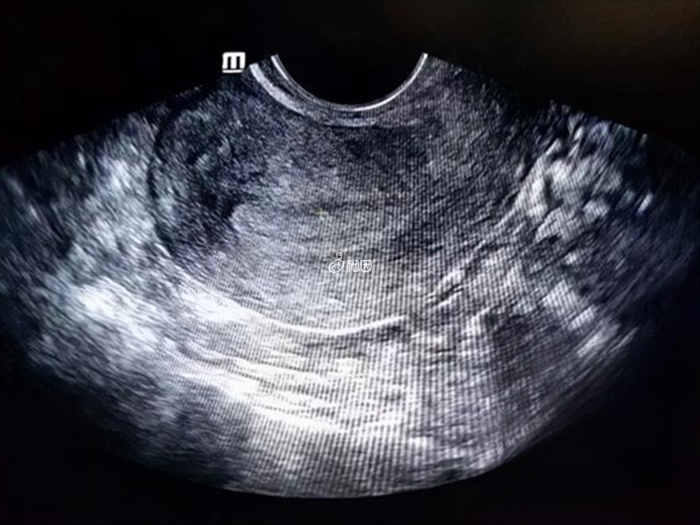

每个月经周期,子宫内膜随着卵泡发育分泌的激素而增长。例如:增生期子宫内膜约9~10mm;分泌期子宫内膜约5~6mm;月经期子宫内膜约8~10mm。这种生理性的增厚是正常的,没有危害的。而一般评估内膜厚度,均应在卵泡发育成熟时进行。如果在无排卵的周期观察内膜,厚度常常是不会达标的,因此,不能仅凭非排卵期的一次超声认为“子宫内膜薄”。

通常情况,在做试管婴儿时,是以排卵前日或胚胎移植日检测的子宫内膜厚度作为评估指标。